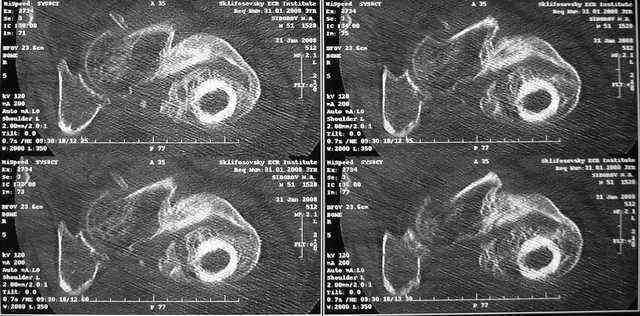

Очень признателен Вам за ответ, но позвольте мне не согласиться с Вами. Я бы пока не делал вывод о анкилозировании тазобедренного сустава. На рентгеновских снимках, да и по данным компьютерной томографии (а этот метод один из самых современных и информативных), хорошо прослеживается постоянной ширины щель между головкой бедренной кости и вертлужной впадины. Кроме того, несложно увидеть разницу "шеечно-диафизарного угла" до и после выполнения тракции в аппарате. Хотя, Алексей, даже если я и прав, это не сильно облегчает нашу задачу.

Какие были движения в суставах до наложения аппарата? Нет ли КТ с 3D?

Дорогие Александр Николаевич и Алексей Владимирович, вы конечно же правы. Если планировать остеосинтез, то надо сделать более точную репозицию. Планируем этим заняться в ближайшие дни. Алексей Владимирович, движения в тазобедренном суставе были в пределах 10-20 гр. Завтра попрошу у врачей из КТ сделать 3D реконструкции.